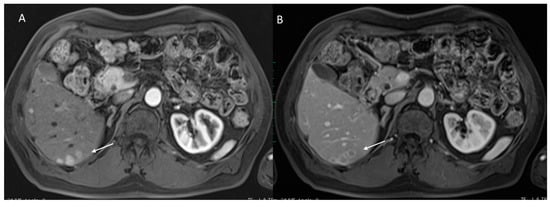

2.4. LI-RADS Treatment Response Algorithm